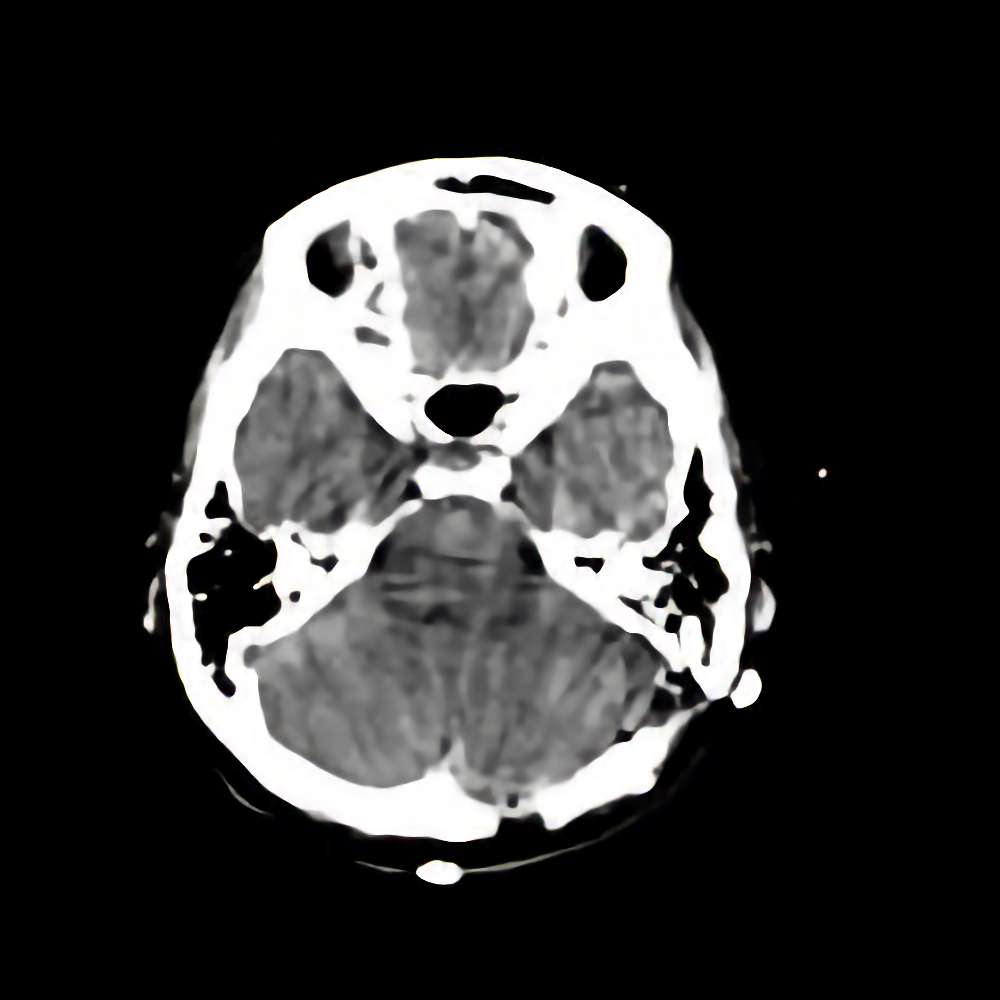

症例 '14年6月

No.

※ 画像をクリックすると拡大表示します。症例No.は平成29年から起算しています。

年_番号

手術年月

患者年齢

’14_104

'14年6月

40代

病名

術式

備考

海綿状血管腫

断層撮影

手術前

1

手術前2

手術後